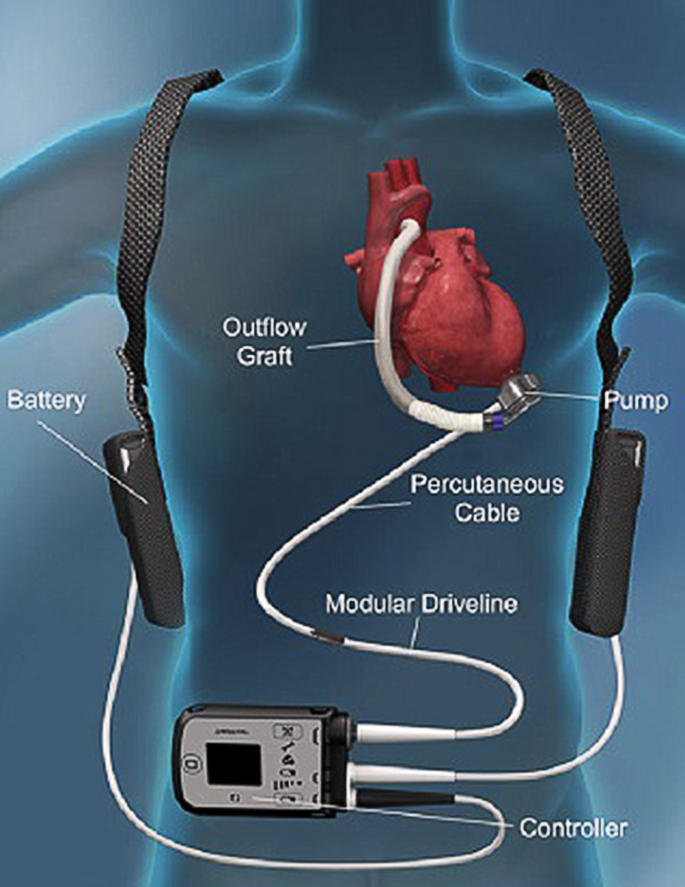

Особенности и диагностика левостороннего кровотока